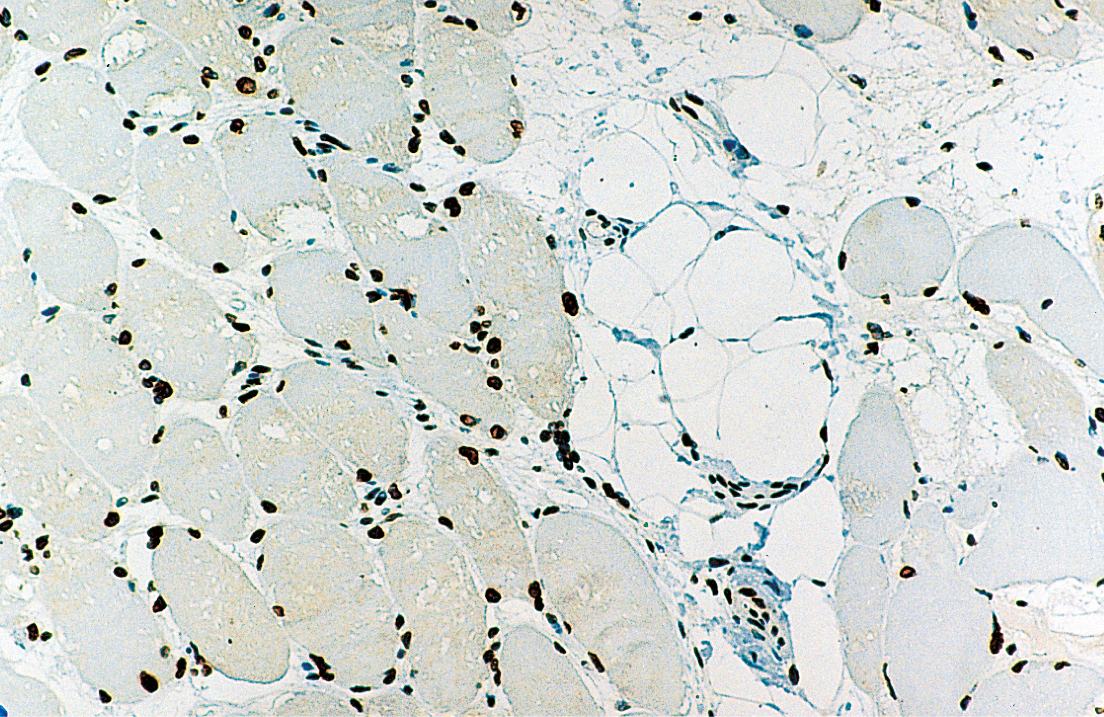

Human skeletal muscle: immunohistochemical staining for Emerin. Note perinuclear staining of all cell nuclei. Emerin: clone 4G5

Emery-Dreifuss muscular dystrophy (EDMD) is a late onset, X-linked, recessive disorder characterized by slowly progressing contractures, wasting of skeletal muscle and cardiomyopathy usually presented as heart block. Contractures are seen in the elbows, Achilles tendons and post cervical muscles with humero-peroneal distribution early in the course of the disease. The STA gene, at Xq28 locus, encodes a serine-rich 34kD protein, emerin, which is ubiquitous in tissues and is found in highest concentration in skeletal and cardiac muscle. Emerin is localized in the nuclear membrane of normal muscle cells and its deficiency plays a crucial part in the pathology of EDMD.